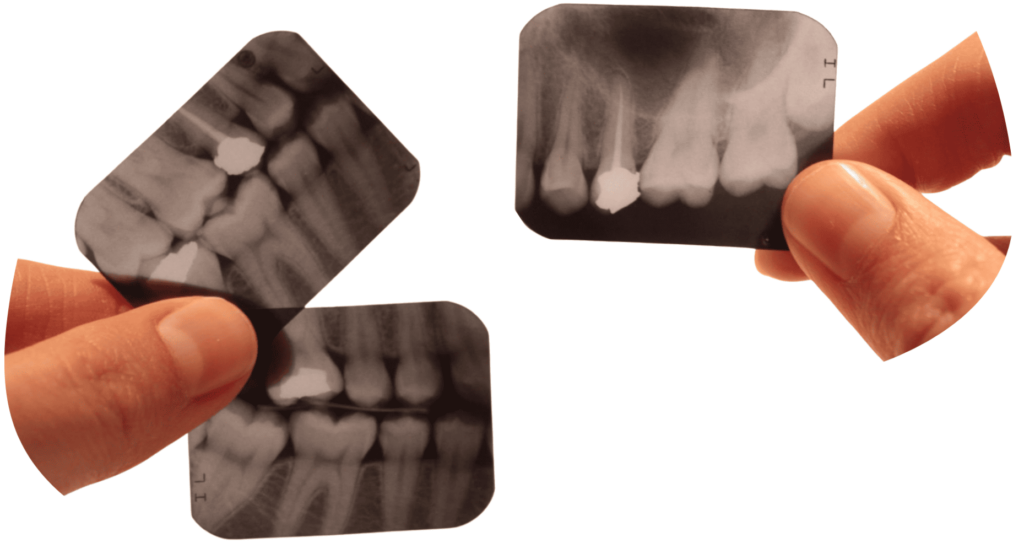

SNIMANJE POJEDINAČNIH ZUBA

Fokusirano snimanje pojedinačnih zuba i ciljanih regija čeljusti posebno je važno u endodonciji, pri analizi korijenskih kanala, fraktura zuba i upalnih procesa.

Snimanjem isključivo potrebnog područja osigurava se visoka dijagnostička preciznost, uz minimalnu izloženost pacijenta zračenju.